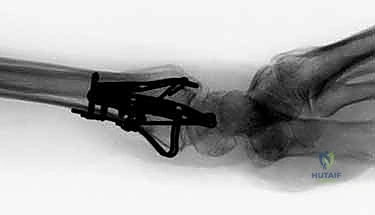

هنا تبرز عبقرية التثبيت المتناسب مع الشظايا (Fragment-Specific Fixation). يعتمد هذا النهج الذي يتقنه الأستاذ الدكتور محمد هطيف على مبدأ بسيط ولكنه معقد في تنفيذه: "لكل شظية عظمية مهمة، غرسة خاصة بها". بدلاً من محاولة إجبار العظم المفتت على التوافق مع صفيحة واحدة كبيرة، يتم استخدام مجموعة من الصفائح الصغيرة جداً (Low-profile mini-plates)، والمسامير الدقيقة، والأسلاك (K-wires) المصممة خصيصاً لتطويق وتثبيت كل عمود أو زاوية تشريحية (مثل شظية العمود الكعبري، أو الحافة الهلالية).

- استقرار ميكانيكي فائق: يوفر تثبيتاً صلباً من زوايا متعددة (Construct stability)، مما يمنع انزياح الشظايا لاحقاً.

- استعادة تشريحية مثالية: يسمح بإعادة بناء السطح المفصلي بدقة متناهية، مما يقلل من خطر التهاب المفاصل التنكسي (خشونة الرسغ).

- حركة مبكرة جداً: بفضل الاستقرار القوي، يمكن للمريض البدء في تحريك أصابعه ورسغه في غضون أيام قليلة من الجراحة، مما يمنع التيبس (Stiffness) ويحافظ على قوة الأوتار.

- غرسات منخفضة السماكة (Low-Profile): الغرسات المستخدمة صغيرة جداً ورقيقة، مما يقلل بشكل كبير من احتكاكها بالأوتار المحيطة، وبالتالي يقلل من خطر التهاب أو تمزق الأوتار بعد الجراحة.

1. المداخل الجراحية (Surgical Approaches)

نظراً لأن الكسر يتم تثبيته من جهات متعددة، قد يستخدم الدكتور هطيف شقوقاً جراحية صغيرة ومدروسة بدلاً من شق واحد كبير.

* المدخل الأمامي (Volar Approach): للوصول إلى الحافة الهلالية والسطح الأمامي لعظم الكعبرة. يتم إبعاد الأوتار والأعصاب (مثل العصب المتوسط) بعناية فائقة.

* المدخل الظهري أو الجانبي (Dorsal/Radial Approaches): شقوق صغيرة إضافية للوصول إلى شظية العمود الكعبري أو الجدار الظهري، مع الحفاظ التام على الأوتار الباسطة.